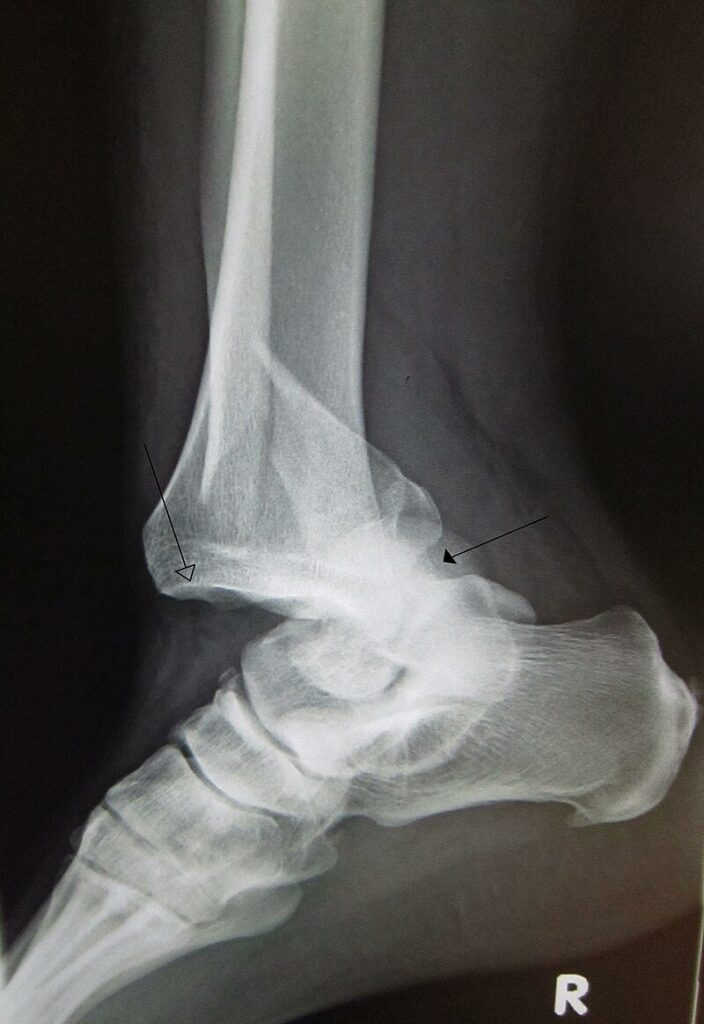

شناخت دررفتگیها و انواع آن

دررفتگی وضعیتی است که در آن انتهای استخوان از محل مفصل خود خارج میشود. این وضعیت معمولاً به دنبال یک ضربه شدید به مفصل رخ میدهد و میتواند بسیار دردناک و ناتوانکننده باشد. شایعترین مفاصلی که دچار دررفتگی میشوند عبارتند از:

دررفتگی زانو: این نوع دررفتگی نادر است اما میتواند بسیار جدی باشد و به بافتهای اطراف آسیب برساند.

هنگام مواجهه با فردی که مشکوک به شکستگی یا دررفتگی است، پزشک ارتوپد باید ابتدا به ارزیابی علائم و نشانهها بپردازد. از جمله علائم شایع شکستگی و دررفتگی میتوان به درد شدید، تورم، تغییر شکل محل آسیب، عدم توانایی حرکت مفصل یا اندام و کبودی اشاره کرد. پزشک ممکن است از روشهای زیر برای تشخیص دقیقتر استفاده کند:

عکسبرداری با اشعه ایکس: یکی از رایجترین و دقیقترین روشها برای تشخیص شکستگی است.

MRI یا سیتیاسکن: این روشها به ویژه برای بررسی شکستگیهای پیچیده یا آسیبهای مربوط به بافتهای نرم مورد استفاده قرار میگیرند.